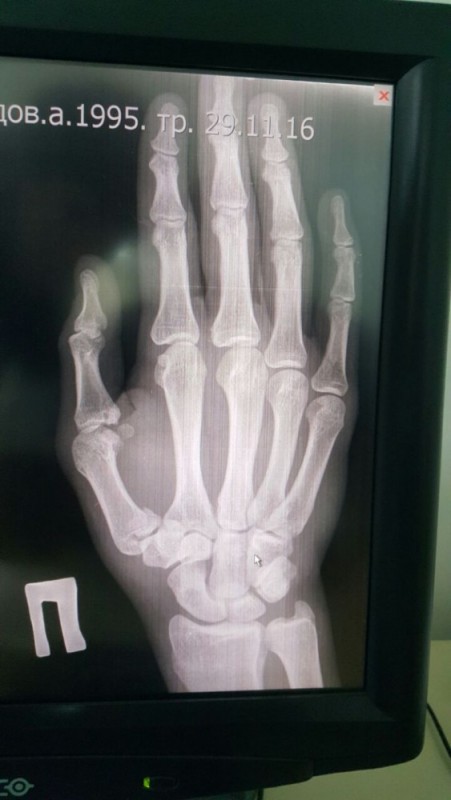

"Я хотел закончить бой в Польше досрочно. Но в связи с переломом правой руки пришлось боксировать только левой рукой. Бой был намечен заранее, и отказаться от него я уже не мог. Хотел и сам боксировать, но пришлось работать одной рукой, нашел в себе силы и отбоксировал на характере. Прошел всю дистанцию боя, все раунды. С одной стороны, может быть, и лучше, что так получилось. Мой соперник выдержал настоящий шквал атак. Хоть я работал одной рукой, но в этом бою она заменила обе руки. Я бил много и жестко, а он все принимал и терпел", - рассказал он.

По словам Ахмедова, травму он получил, когда готовился к финалу Кубка Конфедерации и к бою в Польше. "Во время спарринга неудачно нанес удар - получил перелом большого пальца в области кисти. По приезде в Казахстан у меня будет операция, а потом - восстановление. По плану, в конце января я вылетаю в Лондон и буду готовиться к бою уже там", - заявил боксер.